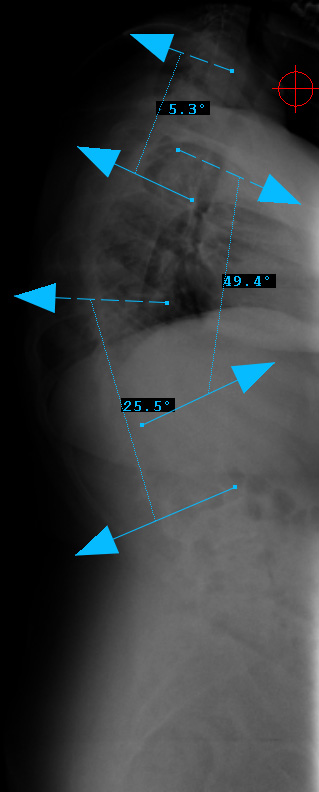

Preop LEFT Bend

Preop RIGHT Bend